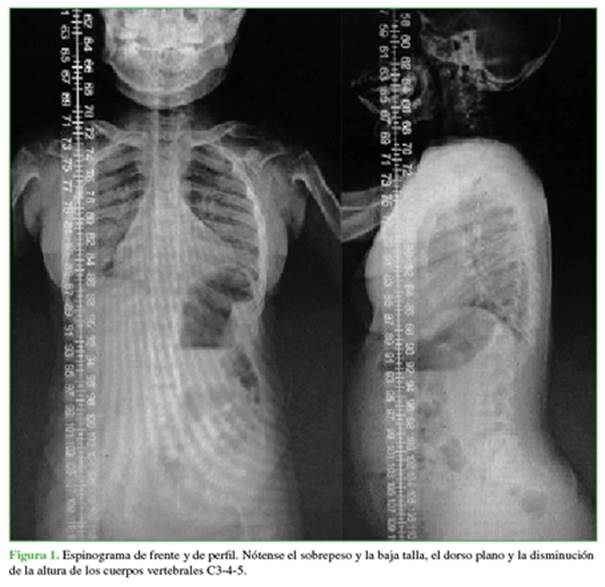

Las radiografías iniciales mostraban una disminución de altura de los cuerpos vertebrales de C3-4-5; además, impresionaba una hipoplasia del proceso odontoides, sin signos de inestabilidad en las radiografías dinámicas (Figuras 1 y 2).